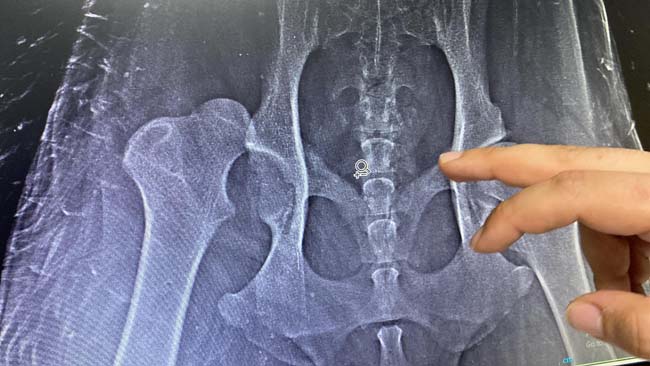

Röntgen filminde uyluk kemiği yerinden çıktığı tespit edilen ve ismi “Şans” konulan köpek ameliyatın ardından ayağa kalkıp yürümeye başladı. Fizik tedavi sürecinin ardından sağlığına kavuşması hedeflenen köpeği her gün ziyarete gelen Çeliktaş, taksi sürücüsü hakkında polise giderek şikayetçi olduğunu söyledi.

Köpeğin güçlü bir darbe ile uyluk kemiğinin yerinden çıktığını söyleyen veteriner hekim Ömer Faruk Alkan, “Bu kemiğin çıkabilmesi için güçlü bir darbe alması gerekiyordu. O darbeyi almış ve eklemden tamamen kemik çıkarılmış. Operasyona girdik ve şu an genel durumu çok iyi. Ayağa kalkmaya ve yürümeye başladı. Yaklaşık 15 günlük fizik tedavi ve bakım sonrasında artık sokağa çıkabilecek duruma gelecek” şeklinde tedavi sürecini anlattı.